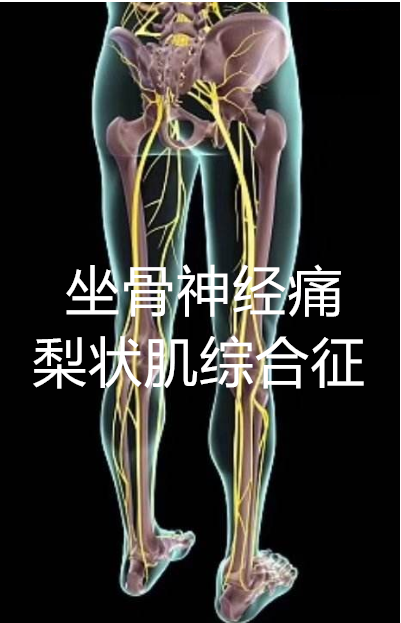

梨状肌压迫坐骨神经

坐骨神经痛不一定都是腰椎间盘突出症,梨状肌综合征不容忽视!

梨状肌属于臀部深层肌肉下方穿梭着坐骨神经当肌肉紧张缩短会压迫到

梨状肌是深层臀肌,而坐骨神经刚好在下方经过.